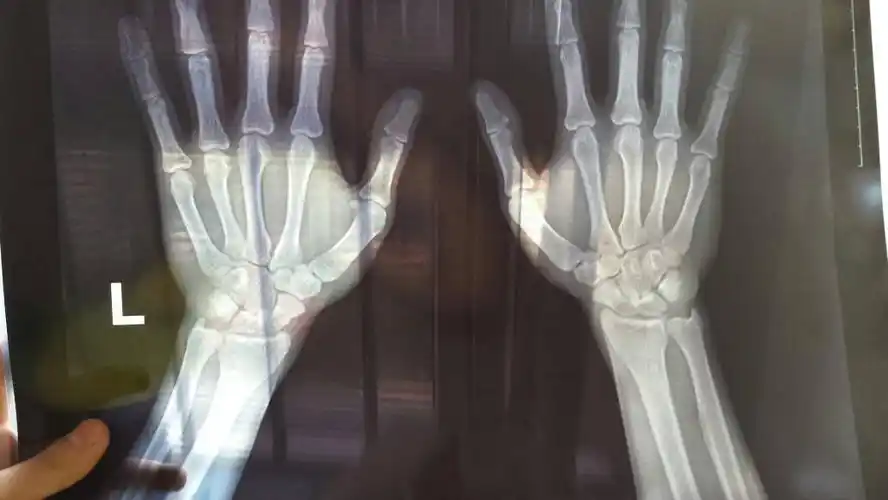

骨骺线闭没闭合对比图

今天去拍了手骨的片子看看骨骺线闭合没,还能长多高,懂的人给我看看吧

请问从x光片上看孩子的骨骺快闭合了吗?还能长多少时间?

医生请帮忙认真看下骨骺线闭合没,非常感谢,顺便问一下,要怎么看?

14岁男孩骨龄16岁,还能长高多少?主要看骨骺线的闭合情况!

应用生长激素的前提是骨骺没有闭合

这是最关键,一切长高都在骨骺线未闭合的基础之上.

骨骺一旦闭合,也就是要结束生长了.